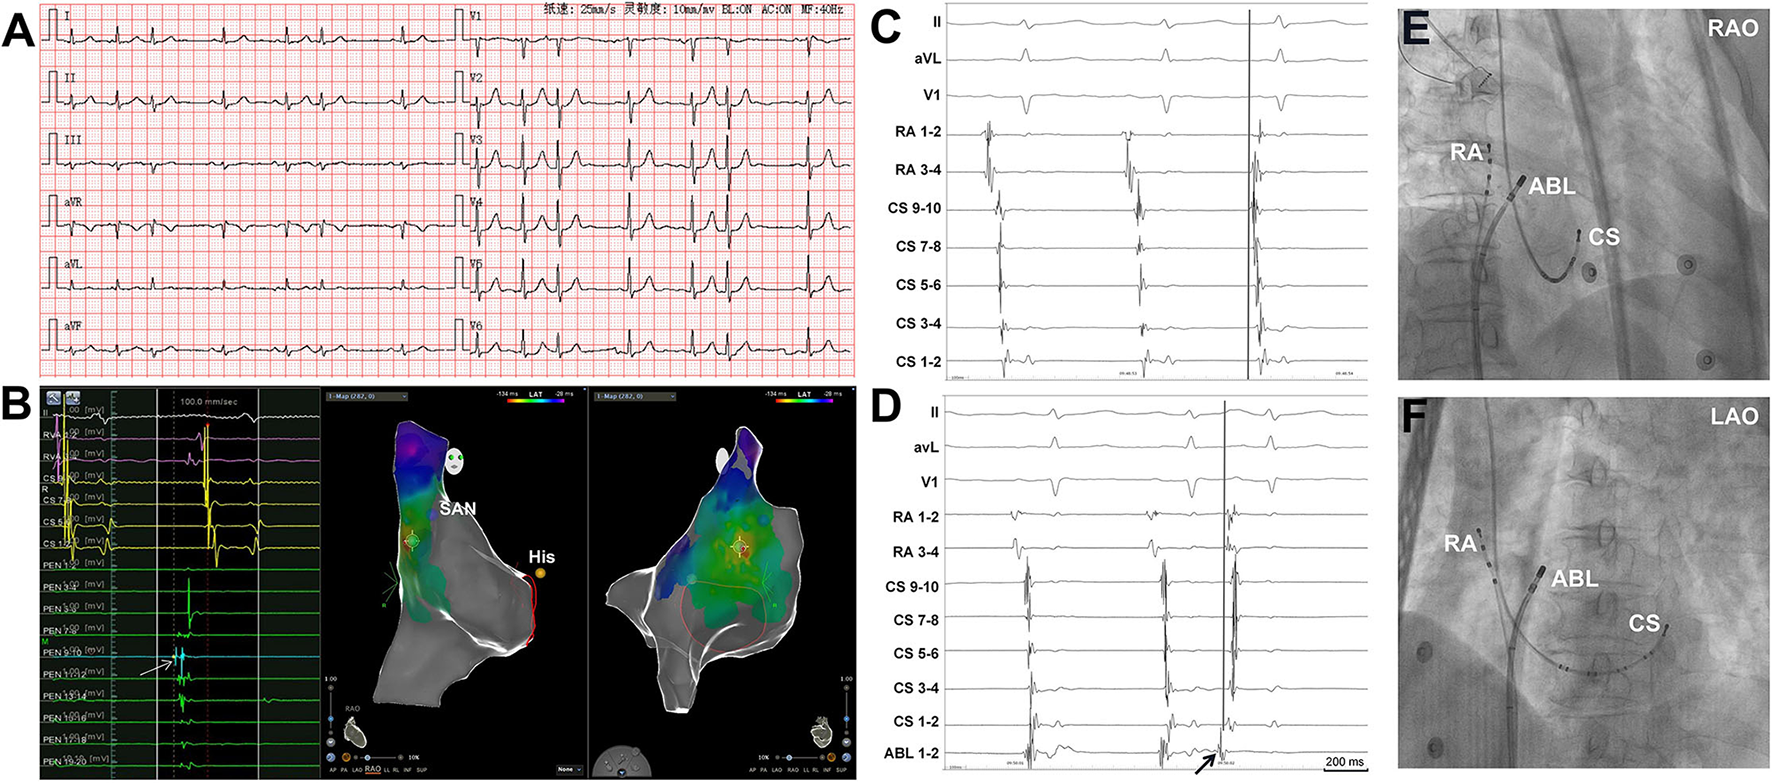

Figure 1

Simultaneous recordings of the right atrium (RA) and coronary sinus (CS) showing the differentiation of spontaneous PACs from PACs induced by catheter manipulation. (A) Surface ECG tracings during spontaneous PACs showing the P-wave morphology. The P-wave morphology in most of the leads is not clearly seen. (B) The 3D mapping shows that the origin site of the PACs is located at the high crista terminalis. The light blue dot indicates the earliest activation point of PACs. The dark blue dot indicates the sinoatrial node. The yellow dot indicates the His bundle. A double sharp atrial potential was recorded in the PentaRay catheter 9-10 (PEN 9-10, the arrow and the light blue dot) and the first atrial potential precedes surface ECG P wave in lead V1 by 40 ms. The RVA channels were connected to the RA catheter. (C) Surface ECG, RA, and CS tracings during spontaneous PAC and PAC induced by mapping catheter manipulation (D). During spontaneous PAC, the proximal RA activation is earlier than the distal RA activation and the atrial activation sequence in CS is from proximal to distal. The proximal RA activation is earlier than the proximal CS activation. During PAC induced by the mapping catheter manipulation (arrow, the catheter was in high RA), the proximal RA activation is almost simultaneous to the distal RA activation and the distal CS atrial activation is earlier than the proximal CS atrial activation. (E) and (F) Radiographs of RA, CS, and ABL catheters. 3D, three dimensional; ECG, electrocardiogram; PAC, premature atrial contraction; SAN, sinoatrial node; ABL, ablation catheter; LAO, left anterior oblique projection; RAO, right anterior oblique projection.